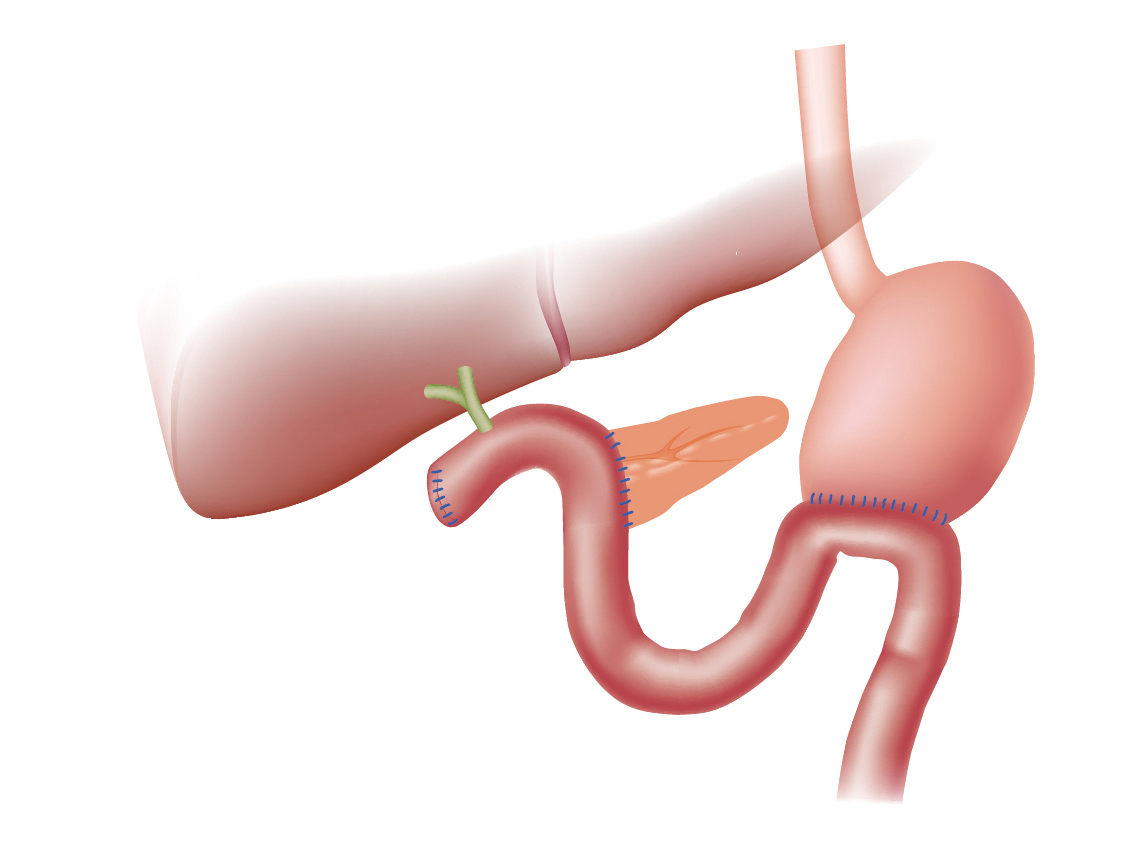

Фотографии медицинских исследований инсулиномы и синдрома Триады Уиппла